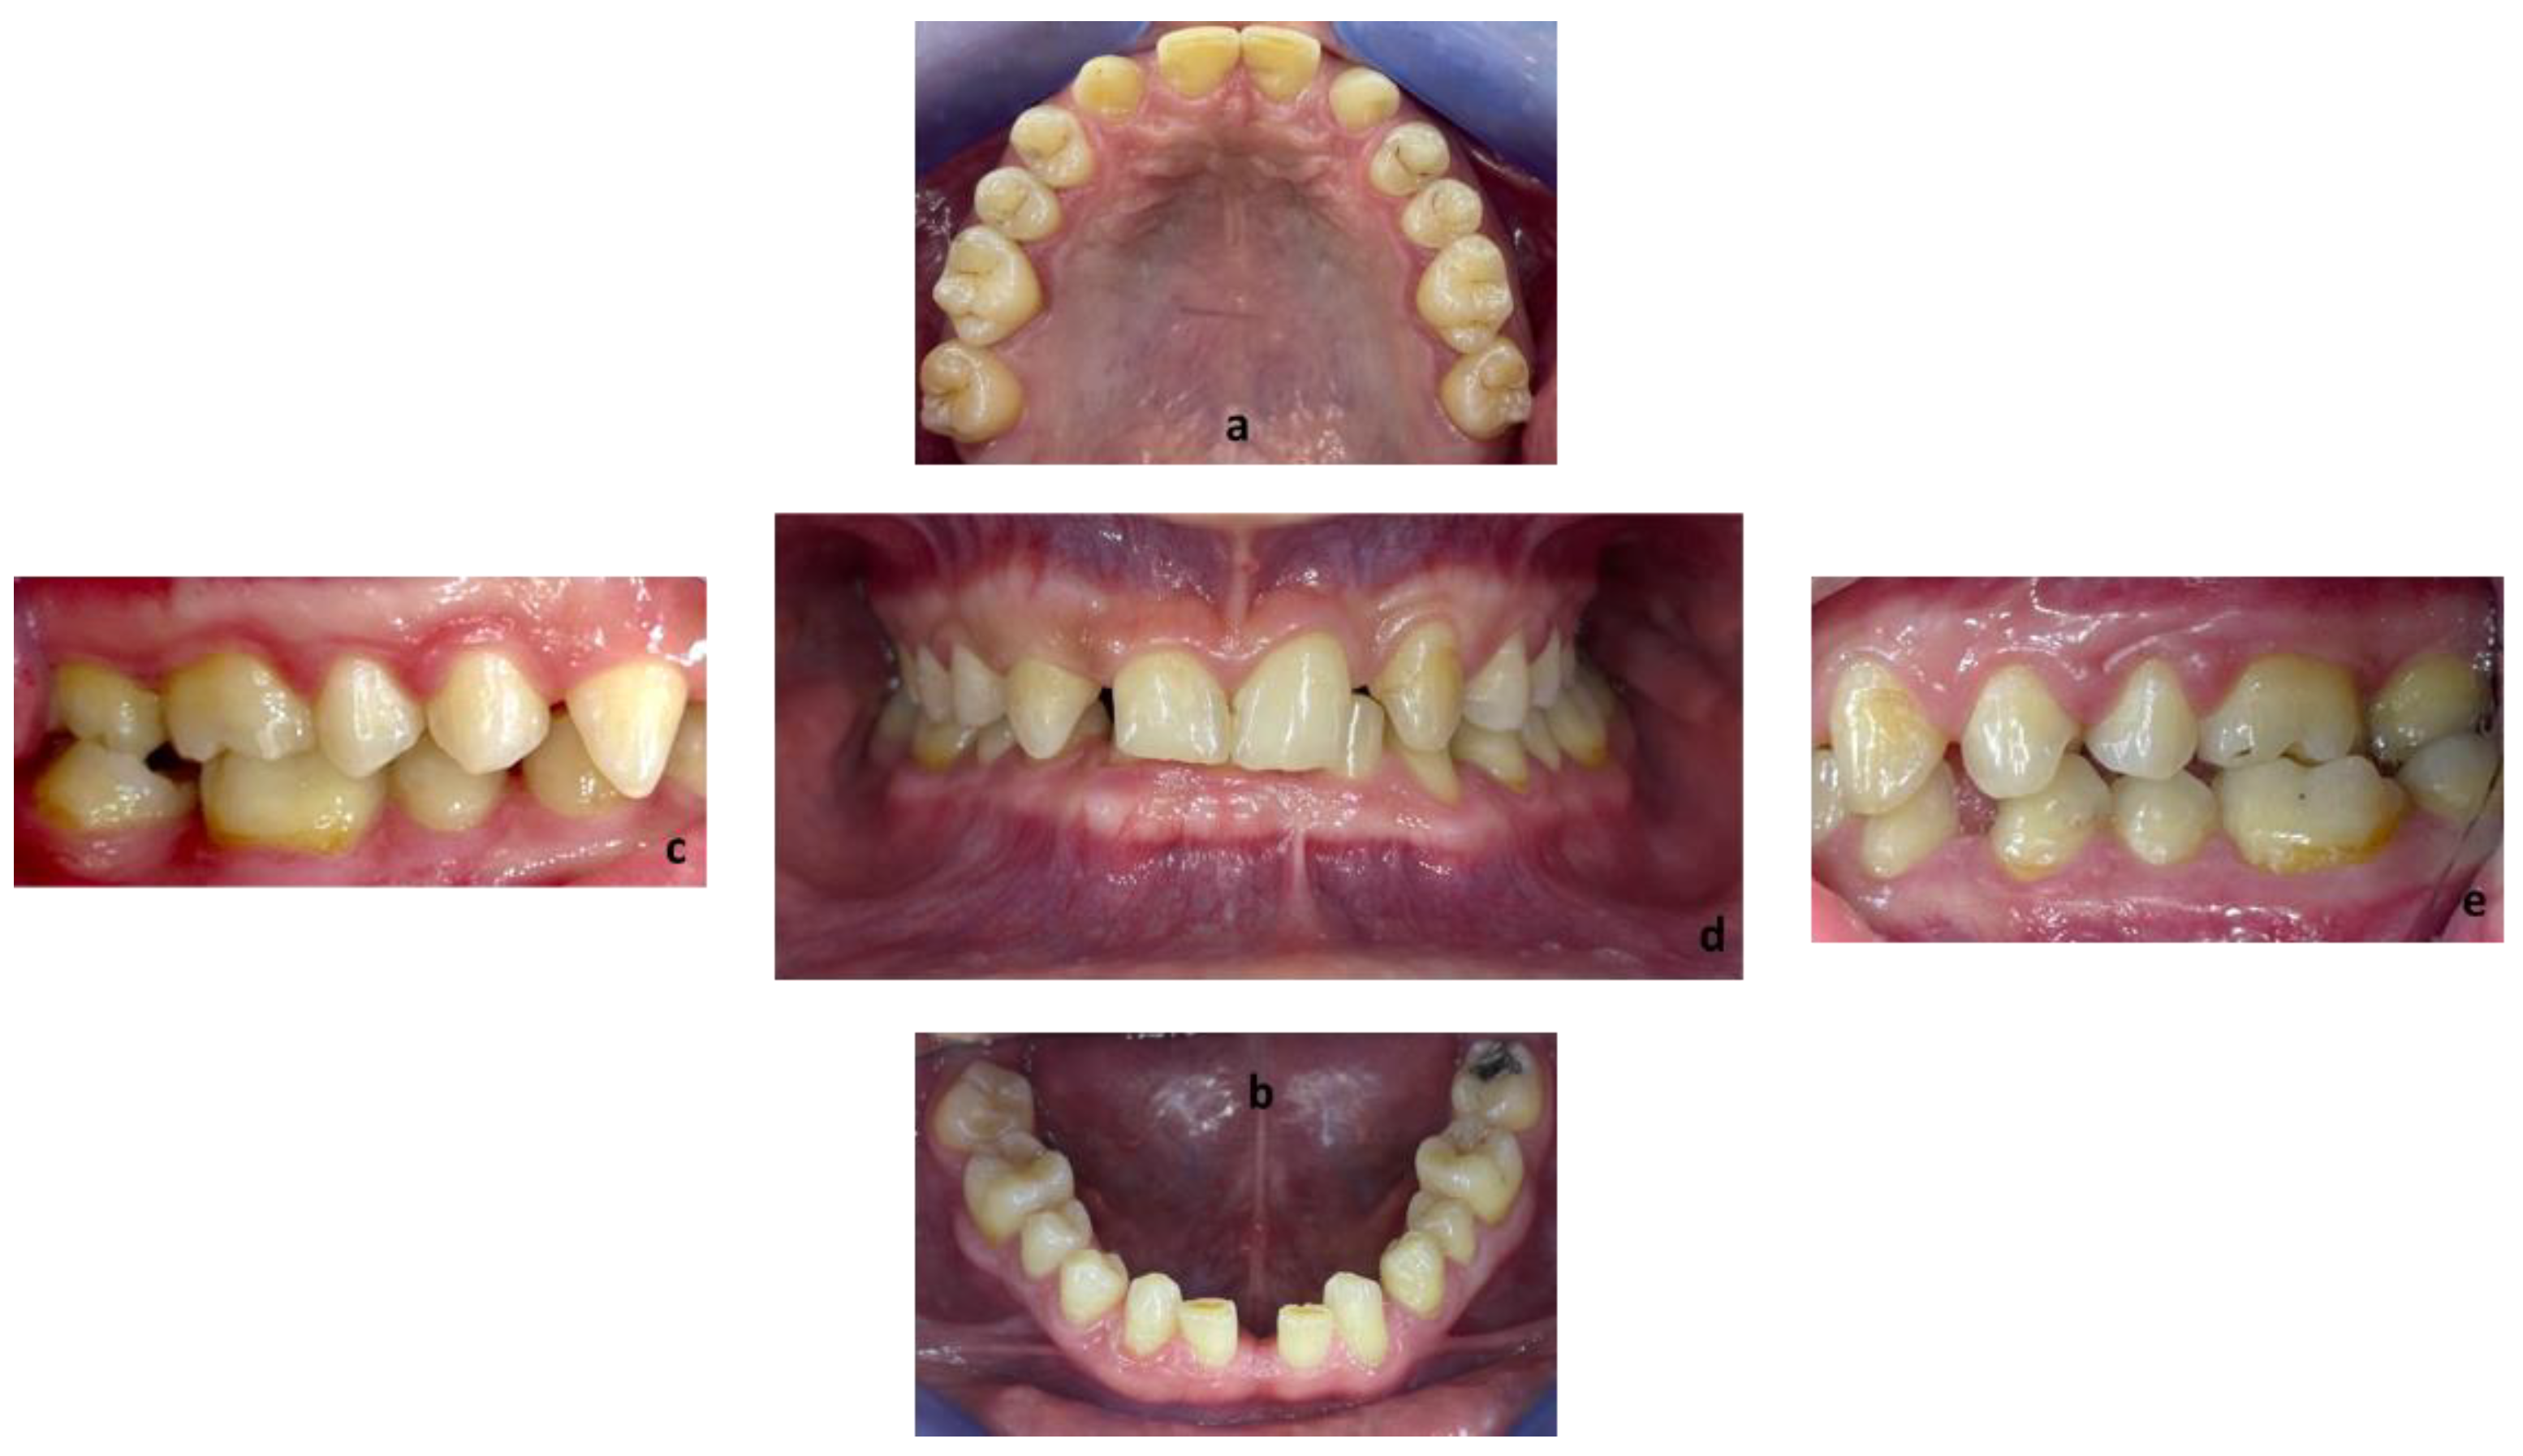

First, alginate impressions were made to obtain diagnostic casts. These casts were mounted in an articulator in order to analyze the case. Face photos and intraoral views were taken and are presented in Figure 1 and Figure 2. The orthopantomogram shown in Figure 3 was realized.

Figure 2.

Endobuccal views: (a) maxillary arch, (b) mandibular arch, (c) right side occlusion, (d) front bite, (e) left side occlusion.

Endobuccal clinical assessment revealed dental agenesis of the upper left and right lateral incisors and lower left and right central incisors, generalized small teeth size, infiltrated maxillary grooves, and an amalgam restoration on the occlusal surface of the lower left second molar. Occlusal analysis showed complete overbite, a left unilateral articular inversion on the two upper left molars, an Angle Class I canine and molar on the right side and an Angle Class II canine and molar on the left side. In addition, the anterior overhang is reduced, so the patient is in class II division 2.